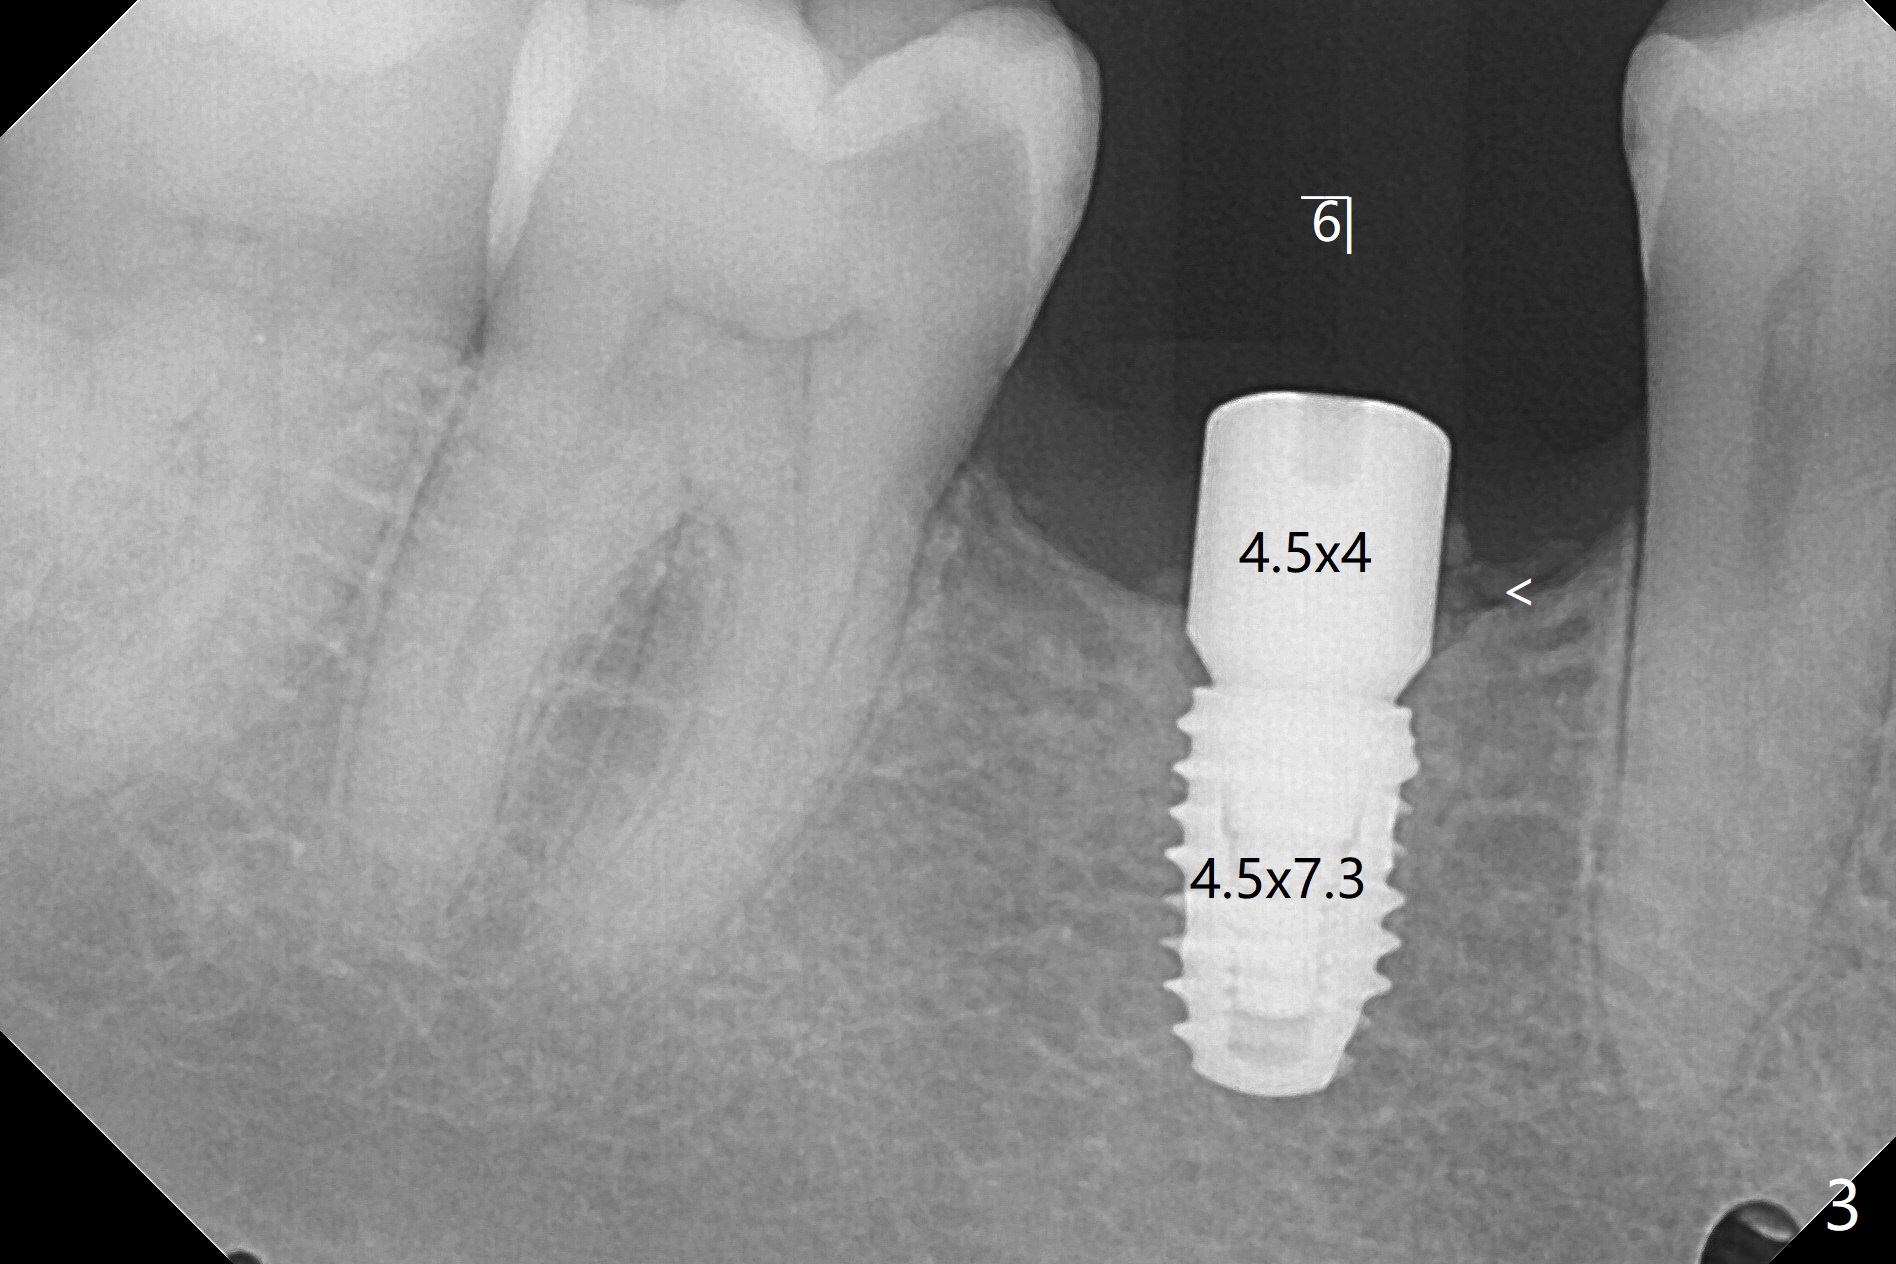

左下植体4毫米,放置4.5毫米愈合基台,不能就位,最后放置4毫米基台,完全入位(图一,二)。右下植体植入后,使用6毫米profile钻头,放置4.5毫米基台没问题(图三)。

术后7个月左下4毫米修复基台无法就位(图四:箭头),局麻下使用4.6毫米Profile钻头后(去除软硬组织阻挡),4.5毫米修复基台顺利就位(图五)。右下第一次手术已经应用Profile钻头,牙槽嵴吸收,所以放置4.5毫米修复基台没问题(图六)。第一次手术应该使用Profile钻头。